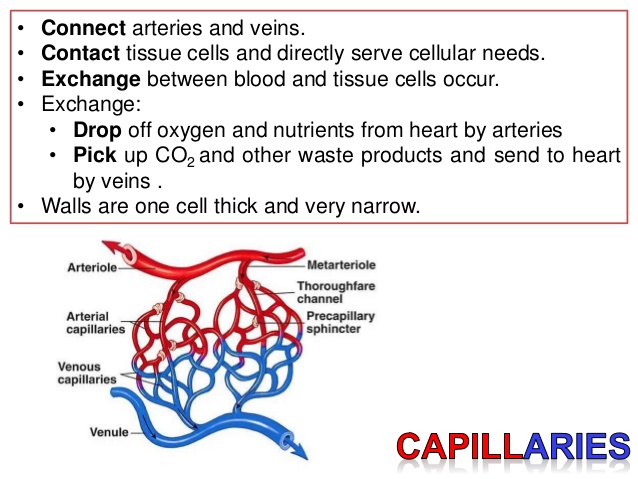

- Blood vessels (arteries, veins, and capillaries)